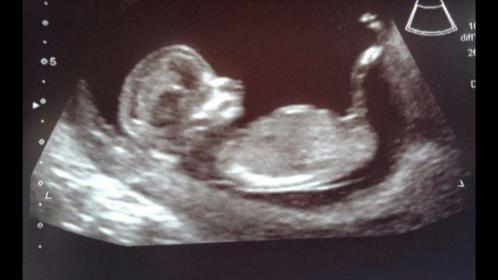

Posting on behalf of a friend who is expecting her 1st child. She is actually 12w 2/3 days in this pic not 13 weeks Excited either way but would love your guesses on what gender she is expecting! Thanks in advance.Attachment 23794

looks like a nub on the rise, but it could go either way I think.